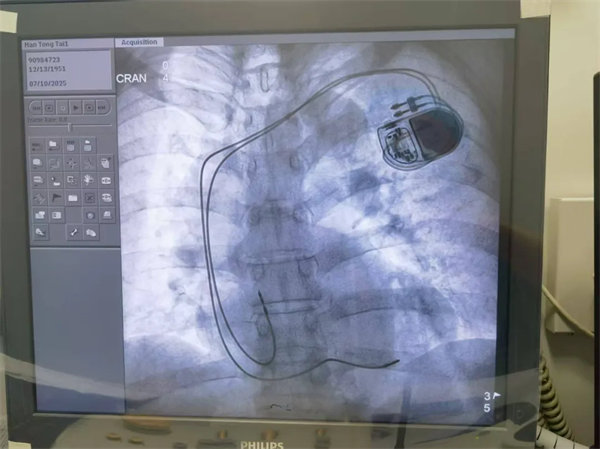

心血管內一科團隊迅速完善心電圖、心臟超聲、動態心電圖等檢查,結合患者病史制定精準診療方案??紤]到藥物治療難以根治,且患者心律失常類型復雜,同時團隊根據患者病情及個人意愿,選擇了進口雙腔永久抗核磁起搏器,于是團隊決定為其實施雙腔永久起搏器植入術。

7月10日,在白志生的主刀下,手術順利完成,成功為患者植入起搏器以維持正常心率。術后經過抗動脈硬化、抗心律失常等藥物治療及精心護理,患者心率穩定在60-85次/分,各項指標逐步恢復正常,8天后便康復出院。

術后患者恢復良好